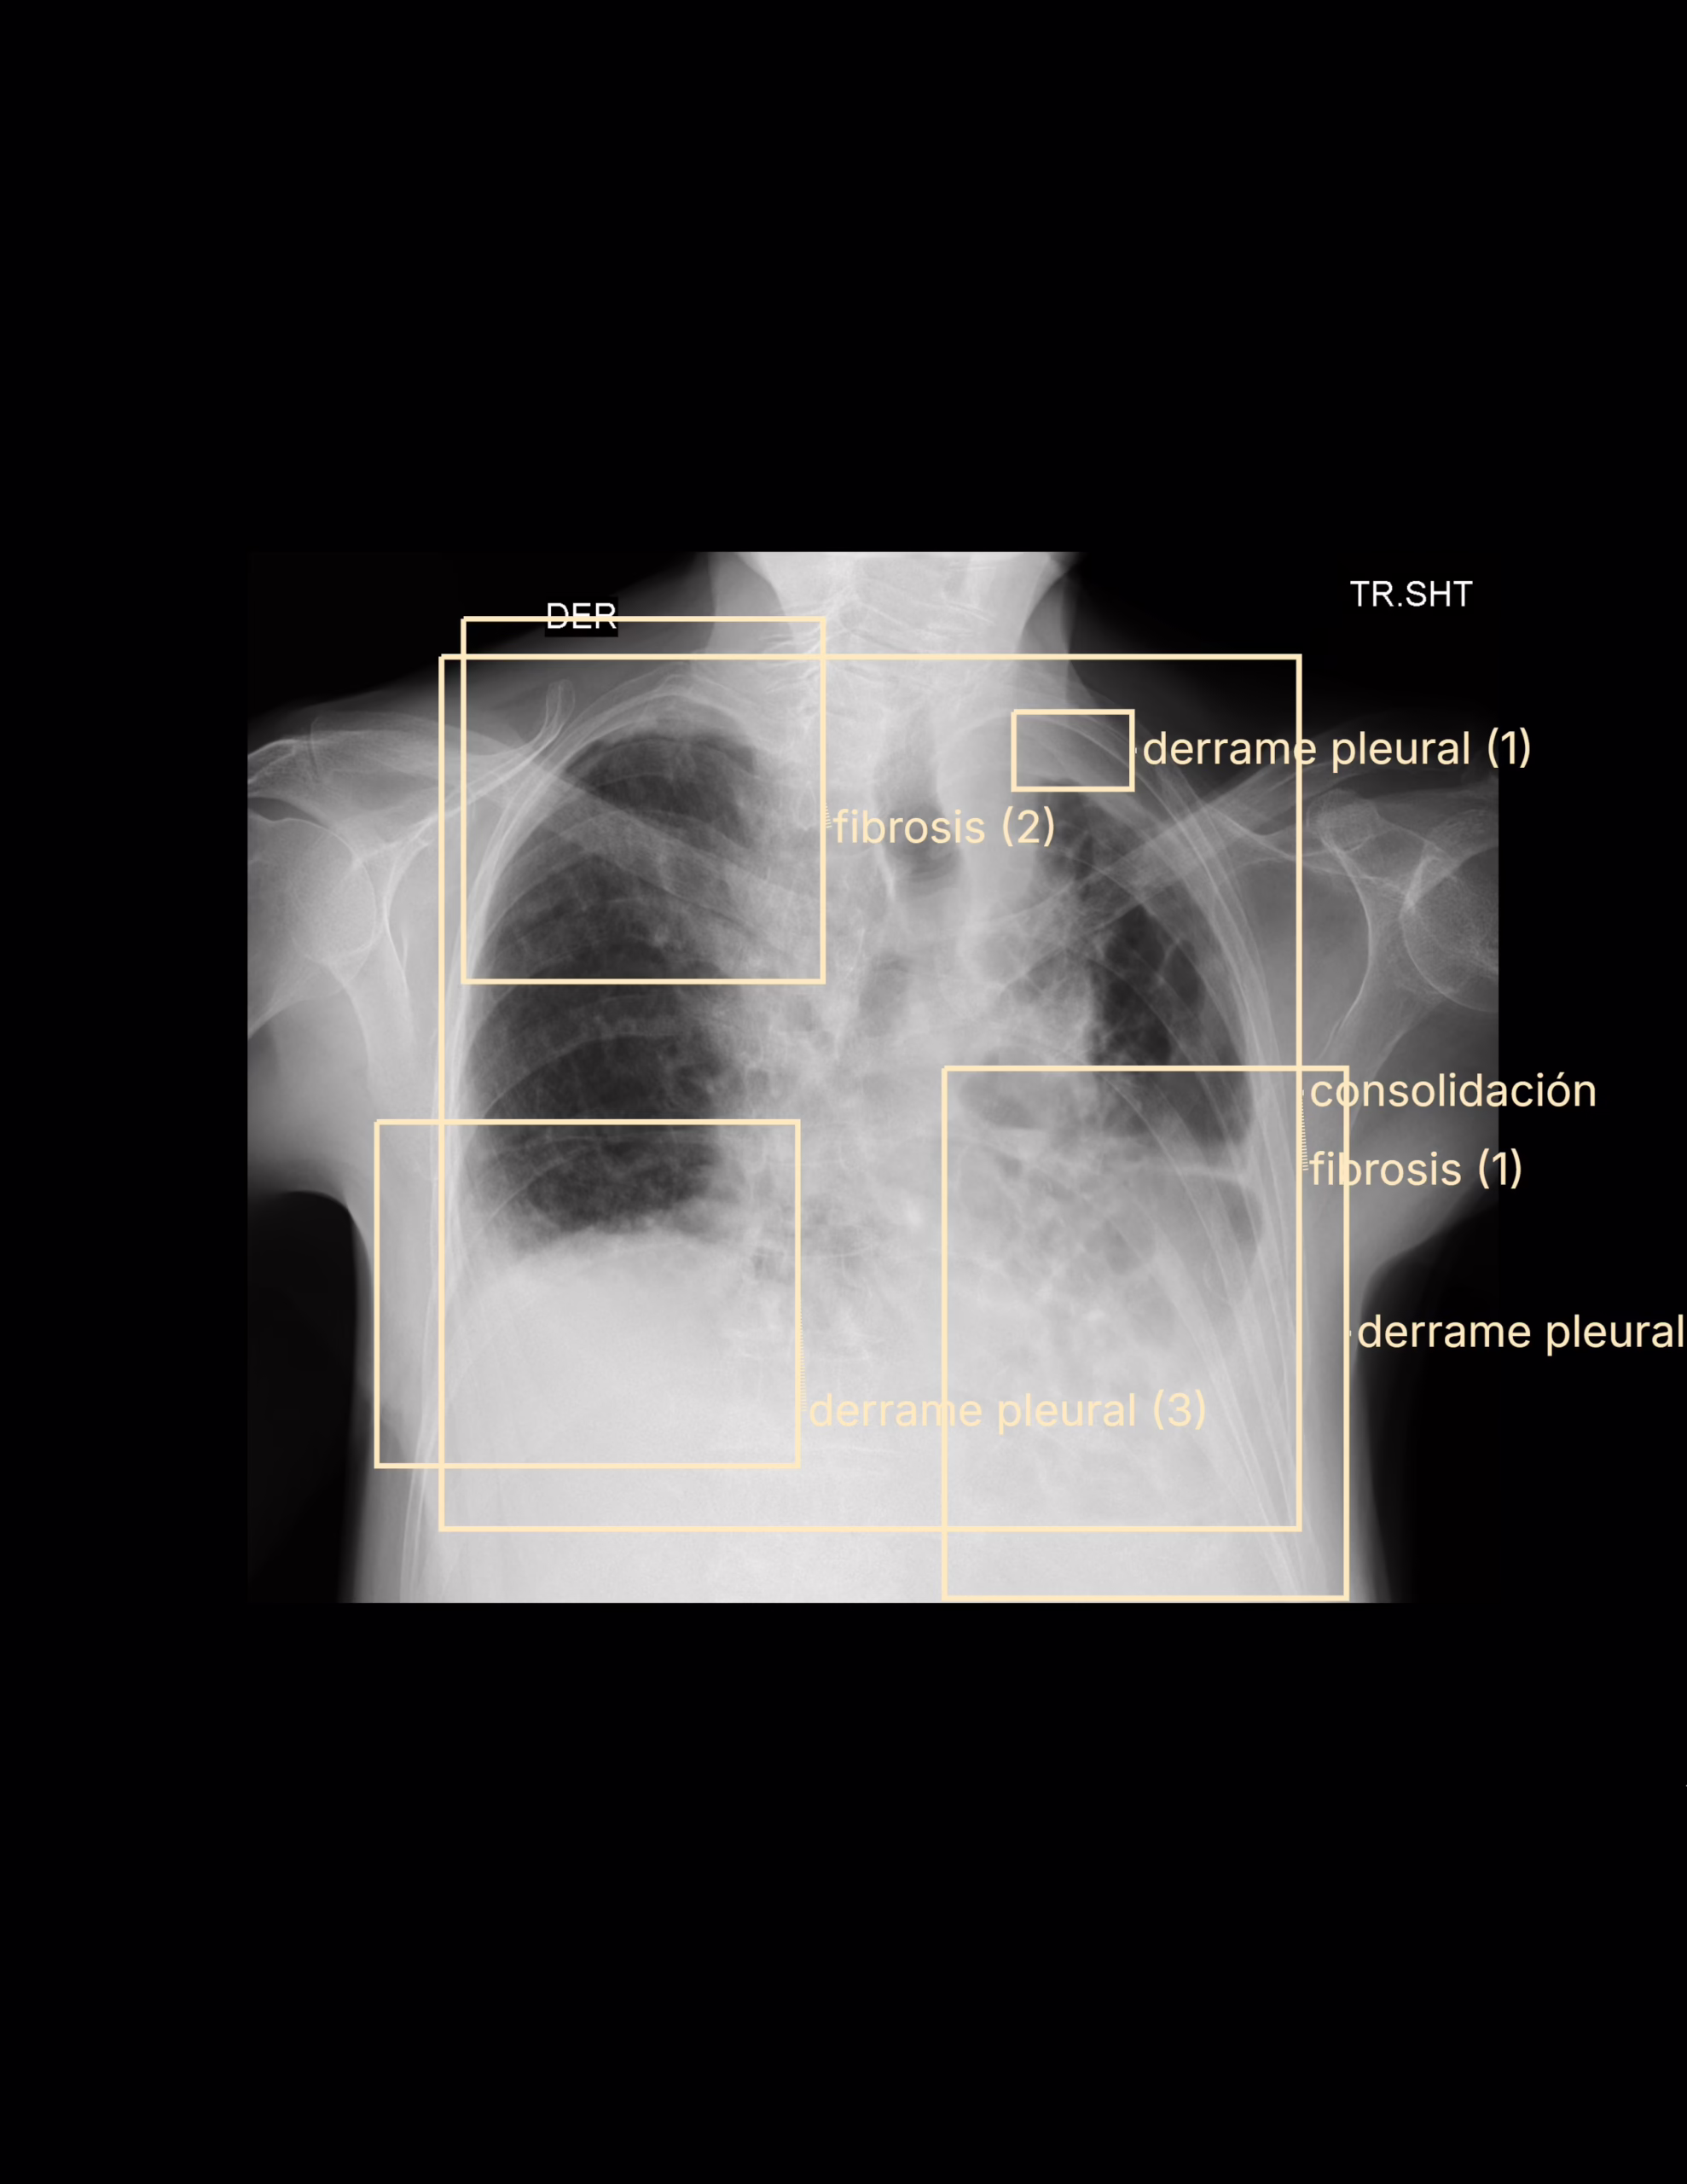

LA PROYECCION RADIOLOGICA OBTENIDA NOS MUESTRA LOS SIGUIENTES HALLAZGOS:

-Trama bronco-vascular, con alteración.

-Campos pulmonares, con opacidad reticular difusa. Así como atelectasias subpleurales distribución aleatoria periférica de predominio en pulmón izquierdo, que disminuye en el volumen de parénquima pulmonar izquierdo

-Existe ascenso de hemidiafragma izquierdo, propiamente asociado a atelectasias.

OPINIÓN RADIOLÓGICA:

EN EL PRESENTE ESTUDIO RADIOGRÁFICO, EXISTE NEUMOPATÍA CRÓNICA INTERSTICIAL DE PREDOMINIO IZQUIERDO, CON DISMINUCIÓN DEL VOLUMEN PULMONAR IZQUIERDO CON ASCENSO DEL HEMIDIAFRAGMA Y DICEN DE LA TRÁQUEA.